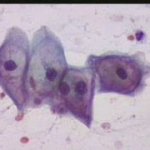

Κυτταρολογικές εικόνες προσβολής του τραχήλου της μήτρας από ιούς κονδυλωμάτων:

Κυτταρολογικές εικόνες προσβολής του τραχήλου της μήτρας από ιούς κονδυλωμάτων: Ασθενής 23 ετών, υποτροπές κολπίτιδος εναλλασσόμενης αιτιολογίας (κολπίτις μικροβιακής αιτιολογίας, κολπίτις από Candida albicans). Τώρα: pH 5, Στο νωπό παρασκεύασμα αρραιή μικροβιακή χλωρίδα. Κολποσκοπικώς επίπεδο μωσαϊκό στο πρόσθιο χείλος. Κοιλοκυττάρωση σε επιφανειακά και διάμεσα κύτταρα. Στην μικροβιοψία τραχηλίτις, υπόνοια για HPV.